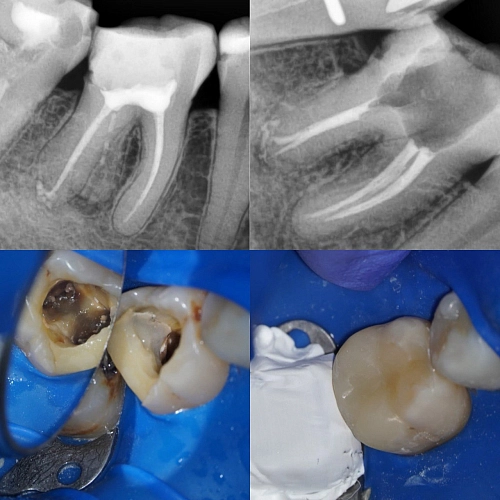

На фото работа врача стоматолога - терапевта - микроскописта Гордеевой Людмилы Валерьевной.

Пациент обратился с жалобами на боль при накусывании и ноющие боли.

При осмотре и диагностике была обнаружена не полная обработка всей системы корневых каналов в связи с чем и произошло инфицирование зуба.

Были найдены, обработаны и запломбированы все 4 корневых канала.

Зуб подготовлен для дальнейшего ортопедического лечения